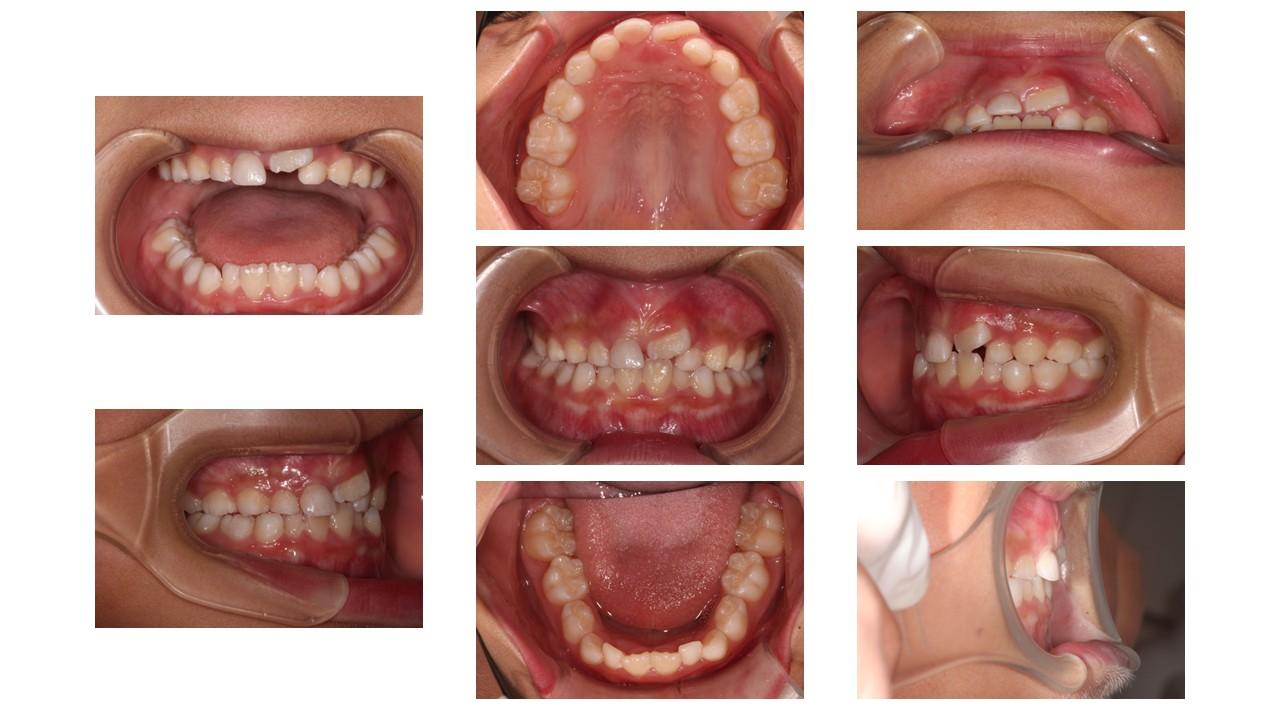

「過蓋咬合」とは、上下の歯の噛み合わせが異常に深い状態のことです。

<正常な噛み合わせ> 上下の歯を自然に噛み合わせたとき、上の前歯は下の前歯を約2〜3ミリ(歯の頭の3分の1程度)覆っているのが理想的です。

<過蓋咬合> 上下の歯を噛み合わせたとき、上の前歯が下の前歯を深く覆いかぶさってしまい、下の前歯がほとんど見えない状態です。場合によっては、下の前歯の先端が上の歯茎に当たってしまうほど深く噛み込んでいることもあります。

【過蓋咬合を治す必要がある理由】過蓋咬合は一見、見た目上大きな問題がないように感じられるかもしれませんが、放置するとお口の健康や全身に様々な悪影響を及ぼす可能性があります。